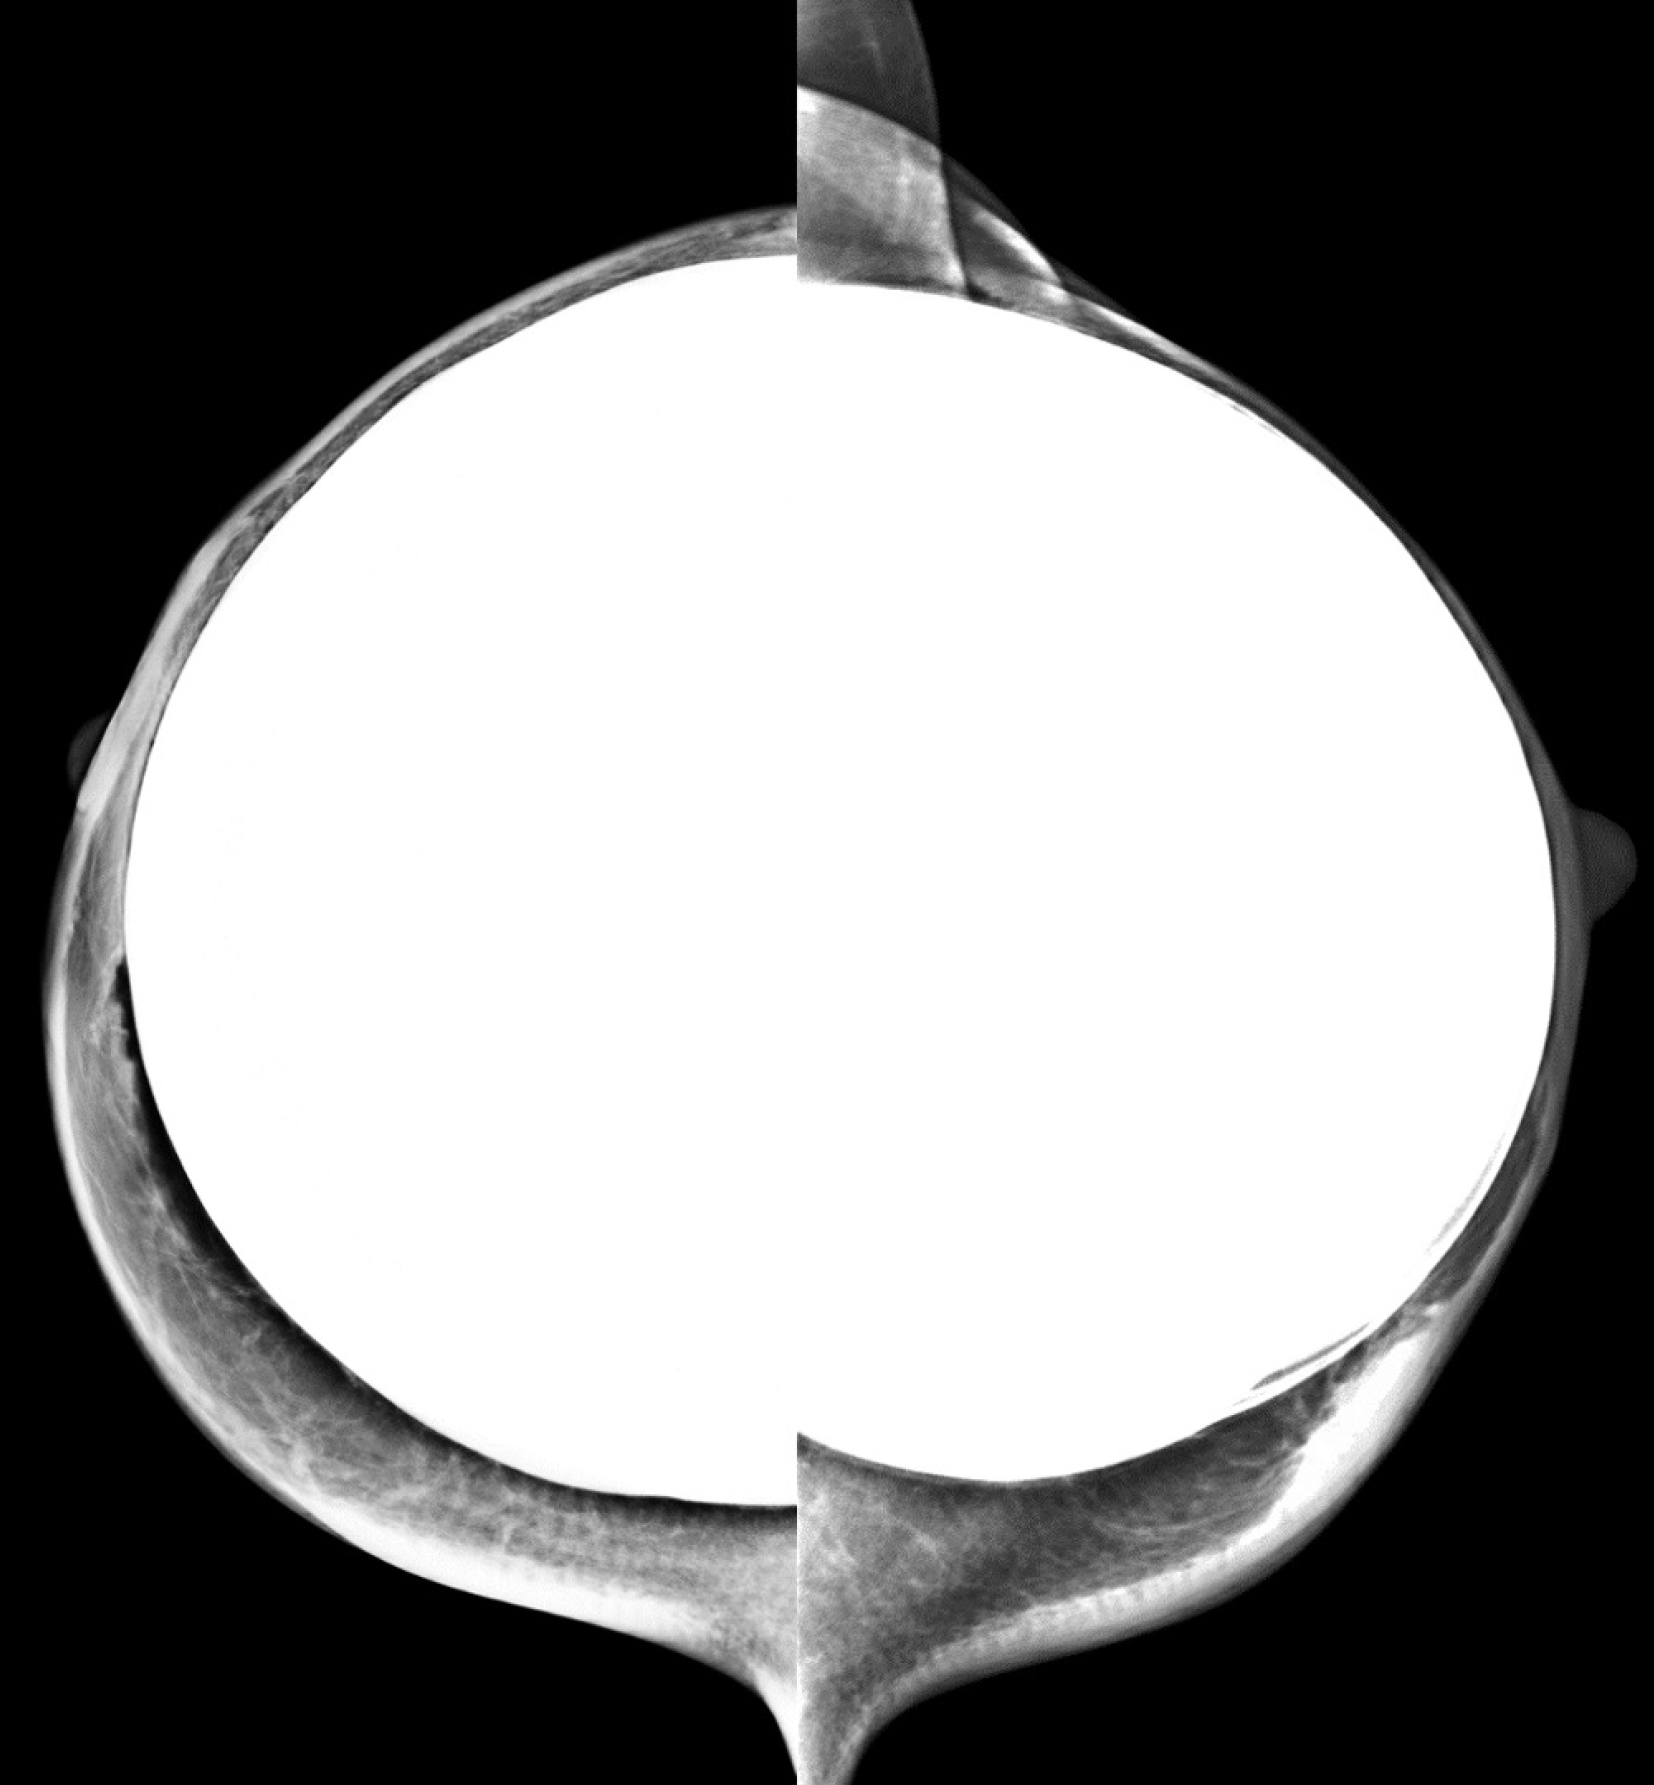

Figure 23

Craniocaudal mammogram of a transfeminine (male to female) individual showing bilateral silicone implants with smooth margins and no signs of rupture.